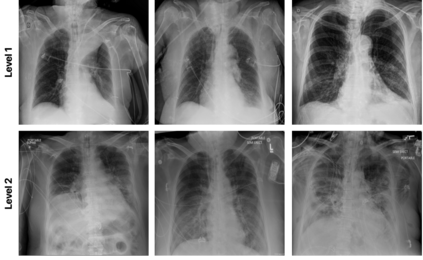

Medical image analysis continues to hold interesting challenges given the subtle characteristics of certain diseases and the significant overlap in appearance between diseases. In this work, we explore the concept of self-attention for tackling such subtleties in and between diseases. To this end, we introduce MEDUSA, a multi-scale encoder-decoder self-attention mechanism tailored for medical image analysis. While self-attention deep convolutional neural network architectures in existing literature center around the notion of multiple isolated lightweight attention mechanisms with limited individual capacities being incorporated at different points in the network architecture, MEDUSA takes a significant departure from this notion by possessing a single, unified self-attention mechanism with significantly higher capacity with multiple attention heads feeding into different scales in the network architecture. To the best of the authors' knowledge, this is the first "single body, multi-scale heads" realization of self-attention and enables explicit global context amongst selective attention at different levels of representational abstractions while still enabling differing local attention context at individual levels of abstractions. With MEDUSA, we obtain state-of-the-art performance on multiple challenging medical image analysis benchmarks including COVIDx, RSNA RICORD, and RSNA Pneumonia Challenge when compared to previous work. Our MEDUSA model is publicly available.